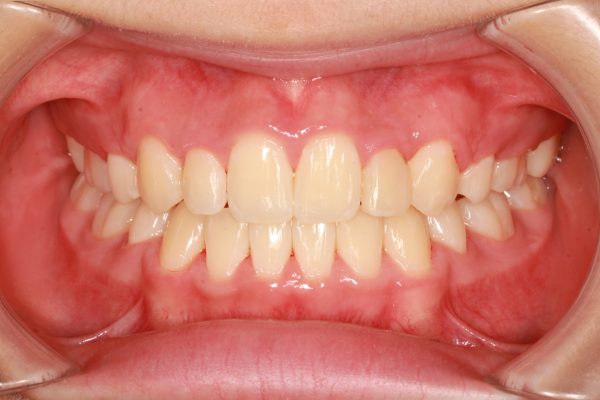

「 前歯、口もとを 治してほしい」 23歳 女性 治療期間22か月(上下顎前突症)

23歳の 女性です。

「 前歯の重なり、口もとを 治してほしい 」との事で来院されました。

前歯の重なりが 強い状態です。

前歯 4本のうち、2本が 反対になっています。

反対咬合の 傾向がある 症例です

前歯が前方に強く傾斜しています。

前歯の状態が 非常に気になるとの事でした。

上下ともに 前歯が傾き、かなり出ている状態です

通常より歯ならびが 前後に長い影響で、歯が前に出ています。

このため、口もとが出ています。

ここまで 口もとが出ていると、自然に口を閉じることが出来ません。

叢生を伴う 上下顎前突症です

前歯の段差と 口もとを治すために上下顎左右の小臼歯抜歯を行い、前歯を後方に移動させました。

2022年1月29日にスタートして 、2024年1月13日に 終 了 しました。

治療期間は22か月でした。

小臼歯の抜歯を行ったことで 前歯が整い、上顎の前後的な距離が適正になりました。

上だけ注目されがちですが、下あごも前後的な距離が短くなり、適正な長さになりました。

上下の顎が適正な長さになった、この効果で上下の前歯が下がりました。

治療前後で前歯の傾斜がかなり改善しました。

レントゲン写真で確認しても上下の前歯は 大きく下がり、

前に飛び出していた上の前歯の傾きが正常化しました。

上下の口唇もかなり下がりました。

口もとの飛び出した感じもなくなり、鼻の下、下唇の形が整いました。

歯ならび が変化したことで、上下の口唇が大きく下がり、あごのラインが綺麗になりました。

口もと の出っ張り感が 解消され、自然に お口が閉じられるように なりました。

前歯の 段差、重なりが 解消し 前歯が 整いました

前歯が キレイ に整い たいへんに満足され、喜ばれていました。